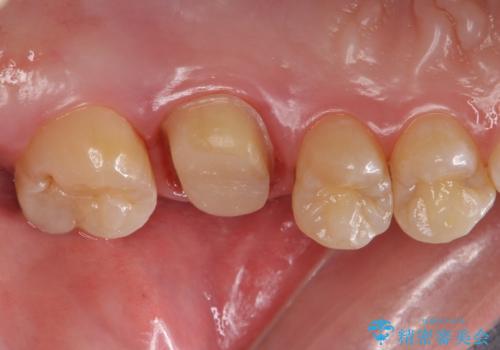

被せ物を除去し、根管治療を進めた後に新しい被せ物を装着していきます。

本来は歯茎をしっかりと下げる外科処置が適応となるケースでしたが、ご希望がなかったため最小限の侵襲に抑えて治療を行いました。

根の中を洗浄し、結果的に適合の良い被せ物をセットすることができました。